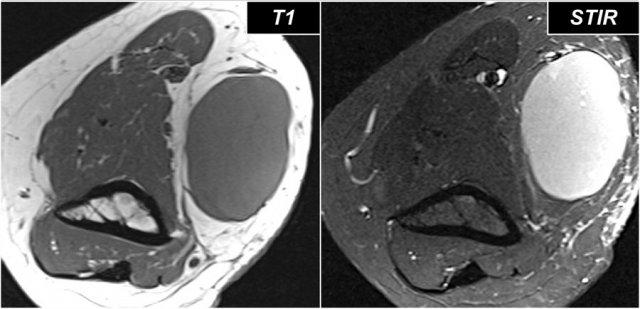

The findings are:

- Trên hình ảnh T1W phía trên bên trái, có tín hiệu cao của mỡ trong các cơ duỗi kèm theo giảm thể tích cơ, điều này cho thấy teo cơ mỡ hóa.

- Hình ảnh cắt ngang ở góc trên bên phải cho thấy một khối u nằm gần hơn trong cơ ngửa.

- The sagittal images confirm that this is a lipoma.

Vì vậy, tình trạng teo cơ là kết quả của sự chèn ép dây thần kinh gian cốt sau, là một nhánh của dây thần kinh quay.